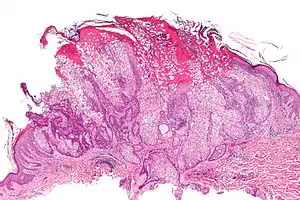

| Micrograph of a sebaceous adenoma. H&E stain. | |